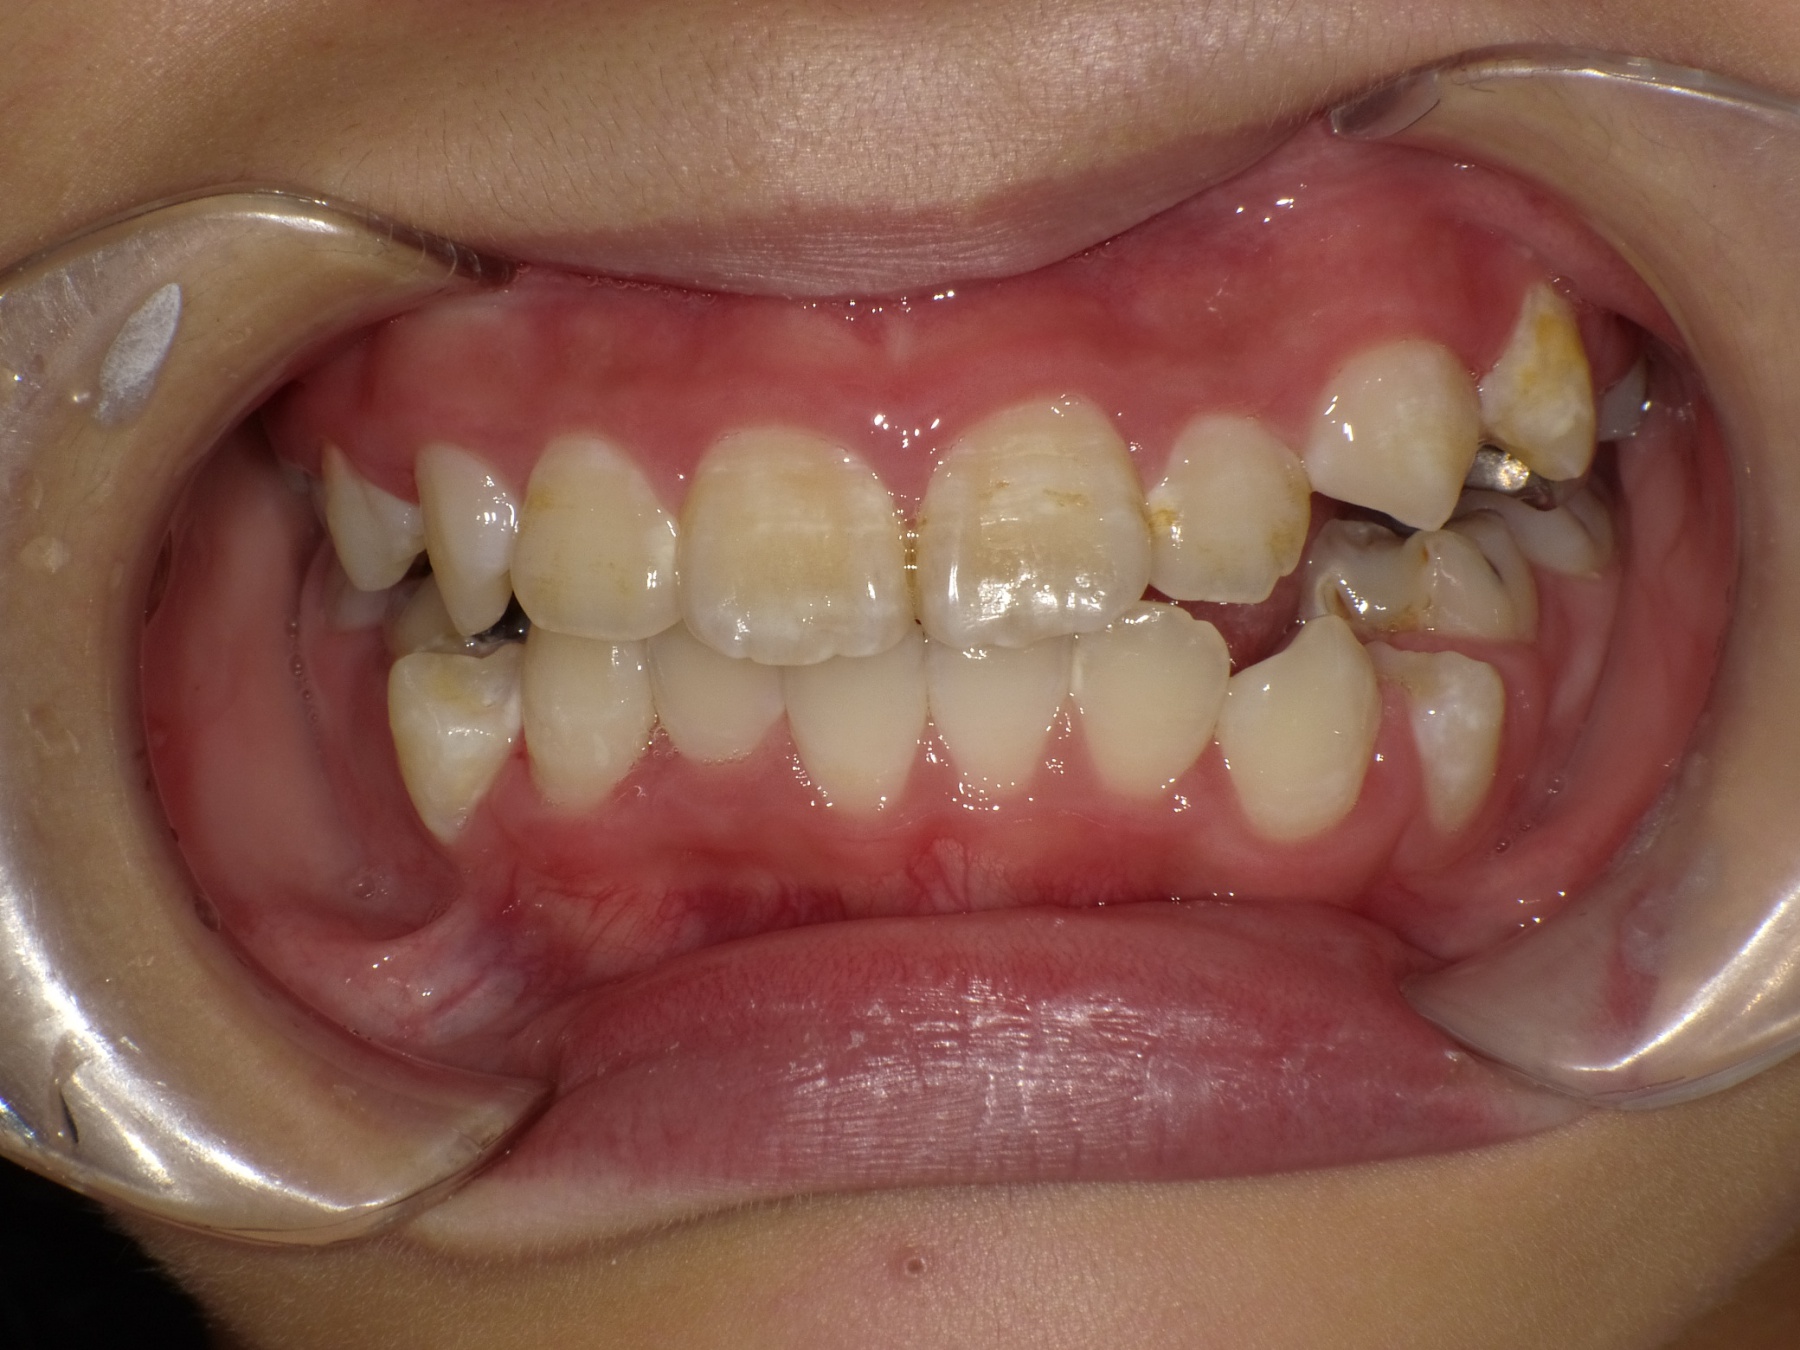

当医院ではお子様の矯正に顎の成長をサポートするような装置を使い、歯ならびを矯正します。

取り外し出来る装置のため、お子様の負担も少なく、気軽に使用できます。

当医院では歯並びだけでなく咬み合わせの確認も行っていきます。

適応年齢は小学生~中学生ですが、それ以前の年齢のお子様も定期健診で様子を診ていきますのでお気軽にご相談下さい。